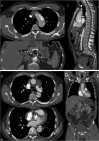

Objectives: To demonstrate the various presentations of acute aortic pathology and to present diagnostic and therapeutic approaches.

Methods: Diagnostic imaging is the key to the reliable diagnosis of acute aortic pathology with multi-slice computed tomography angiography (CTA) as the fastest and most robust modality. Endovascular aortic repair (EVAR) with stent grafts and open surgical repair are therapeutic approaches for aortic pathology.

Results: CTA is reliable in diagnosing and grading aortic trauma, measuring aortic diameter in aortic aneurysms and detecting vascular wall pathology in acute aortic syndrome and aortic inflammation. CTA enables planning the optimal therapeutic approach. Stent graft implantation and/or an open surgical approach can address vascular wall pathology and exclude aortic aneurysms.

Conclusion: Aortic emergencies have to be detected quickly. CTA is the imaging method of choice and helps to decide whether elective, urgent or emergent treatment is necessary with EVAR and open surgical repair as the main treatment approaches.

Teaching points: • To present aortic pathology caused by trauma • To present acute aortic syndrome (aortic dissection, intramural haematoma and penetrating ulcers) • To present symptomatic and ruptured aortic aneurysm • To present infection (mycotic aneurysms/aorto-duodenal fistulae) or iatrogenic injury of the aorta • To understand different presentations for treatment planning (EVAR and open surgery).